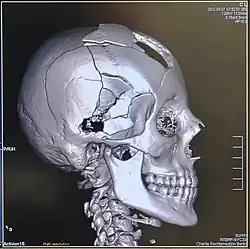

Je nach der Körperregion, in die das Geschoss eindringt, stirbt der Erschossene an einer Herzbeuteltamponade oder an Pneumothorax oder Hämatothorax, an einem Schock oder durch Verbluten. Die Wundballistik ist eine Fachdisziplin der Forensik, die unter anderem vorstehende Umstände genauer untersucht.